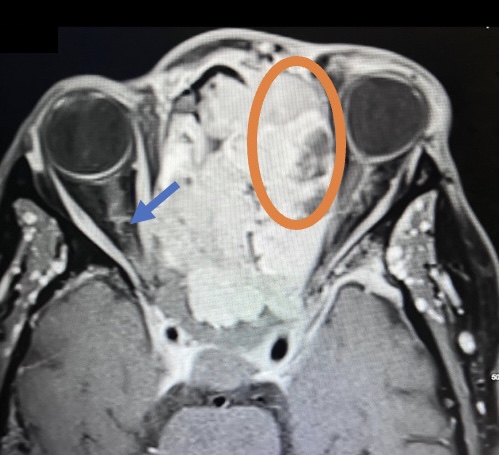

Sinonasal carcinoma is a rare malignancy that often presents with nonspecific symptoms, making early diagnosis challenging. Delayed recognition can lead to disease progression and worse outcomes. This case report emphasizes the importance of early identification, prompt imaging, and multidisciplinary management. A 73-year-old male with a history of anemia and hypertension presented with progressive facial swelling, 20-pound weight loss, and vision loss in the left eye over two months. Initially misdiagnosed with bacterial sinusitis, his symptoms persisted. Examination revealed a proptotic left eye and a large obstructive nasal mass. Computed tomography (CT) and MRI (magnetic resonance imaging) demonstrated a destructive sinonasal mass with skull base and intracranial extension. A biopsy confirmed sinonasal carcinoma, and the patient was started on chemoradiation therapy due to the inoperability of the tumor.

This case underscores the importance of recognizing red flag symptoms such as persistent facial swelling and neurological deficits. Multimodal imaging played a critical role in diagnosis. The literature suggests sinonasal carcinoma is often diagnosed late, reinforcing the need for early suspicion and specialist referral. Sinonasal carcinoma should be considered in patients with persistent facial or nasal symptoms. Timely imaging, biopsy, and interdisciplinary care are essential for optimizing outcomes.